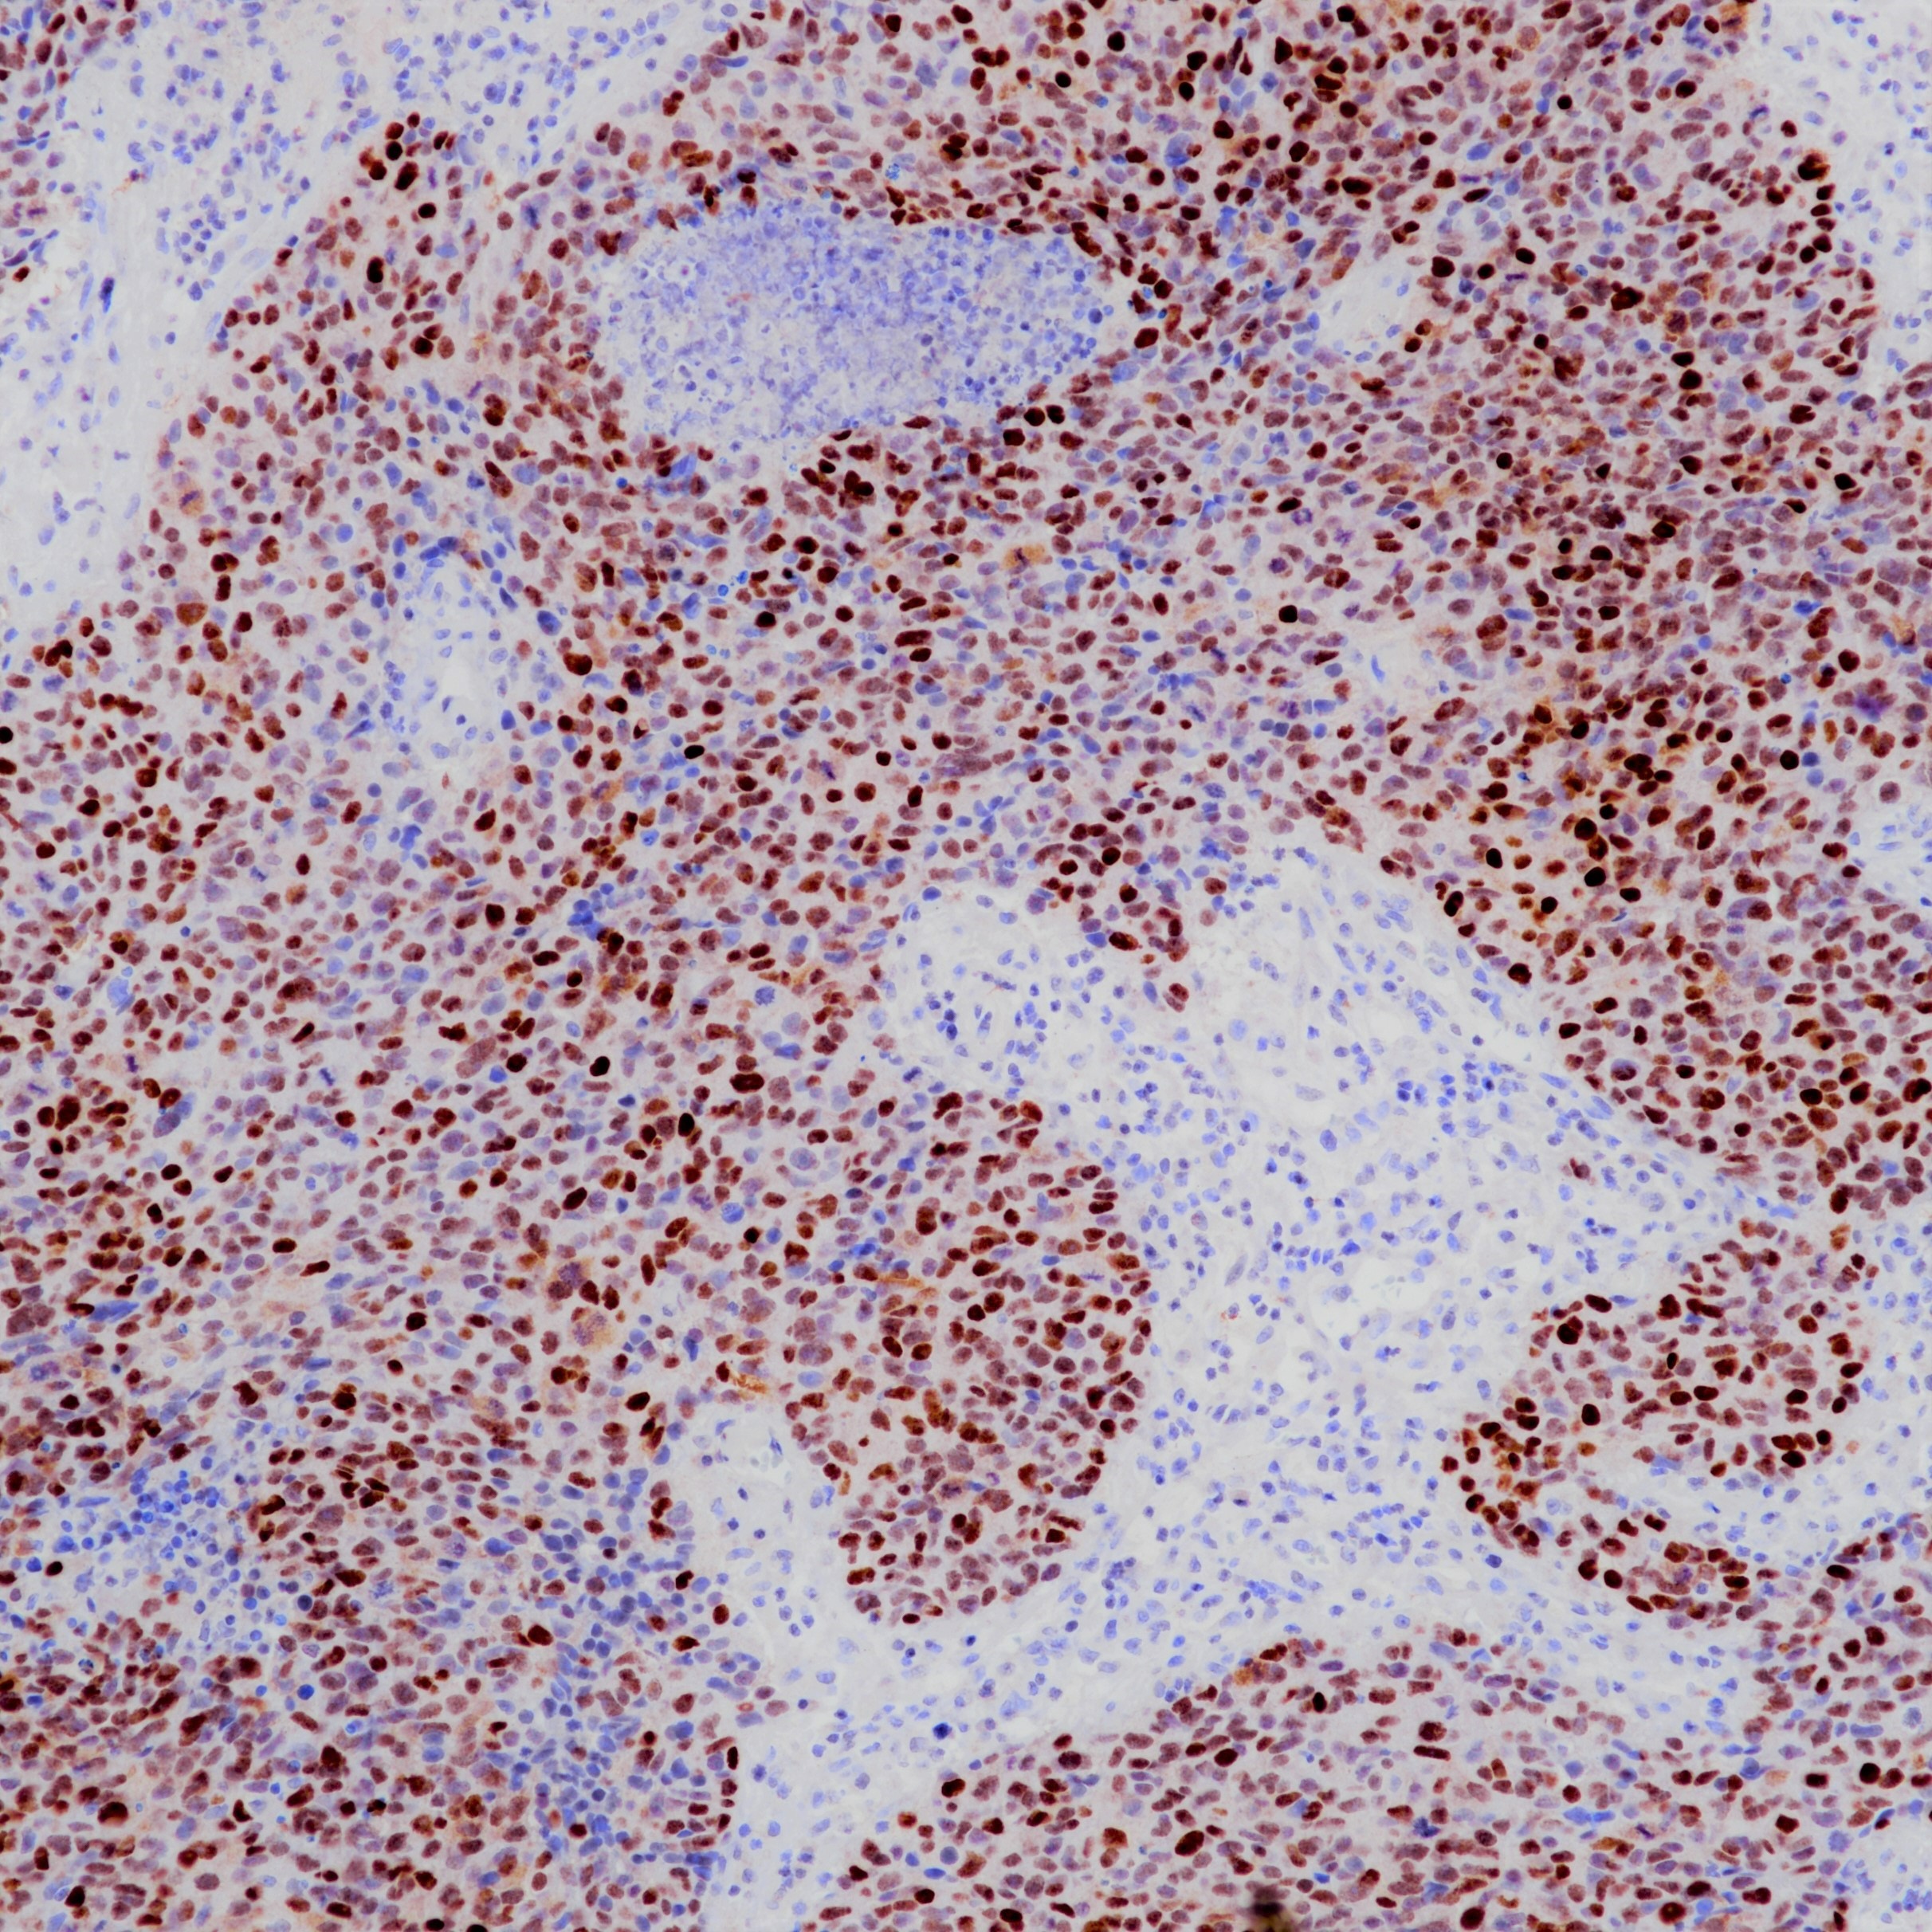

鼻咽癌EBER探针染色

肺癌EBER探针染色

伯基特淋巴瘤EBER染色

EB病毒是一种嗜淋巴细胞疱疹病毒,被国际癌症研究署列为致癌因子之一。EBER是EB病毒编码的小mRNA产物,存在于EB病毒潜伏期、复制期等各个时期。原位杂交检测EBERs能够定位EBV感染的细胞类型,是明确肿瘤与EBV相关的金标准。百凌生物全新推出EBER探针(原位杂交法)试剂,适用于石蜡包埋组织样本及细胞样本,适配LYNX480全自动免疫组化仪器,染色流程经过优化设置,可实现全流程标准化管理,精准快捷高效检出EBER1 & EBER2,明确EBV感染情况。